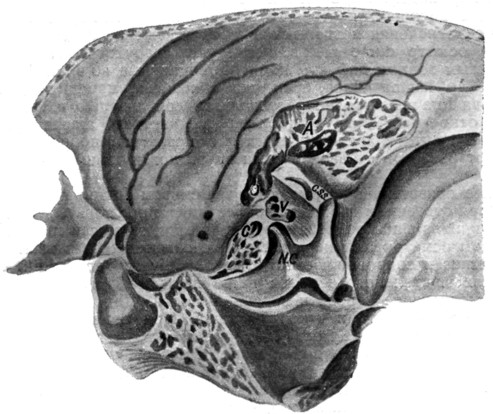

Анатомия сосцевидного отростка